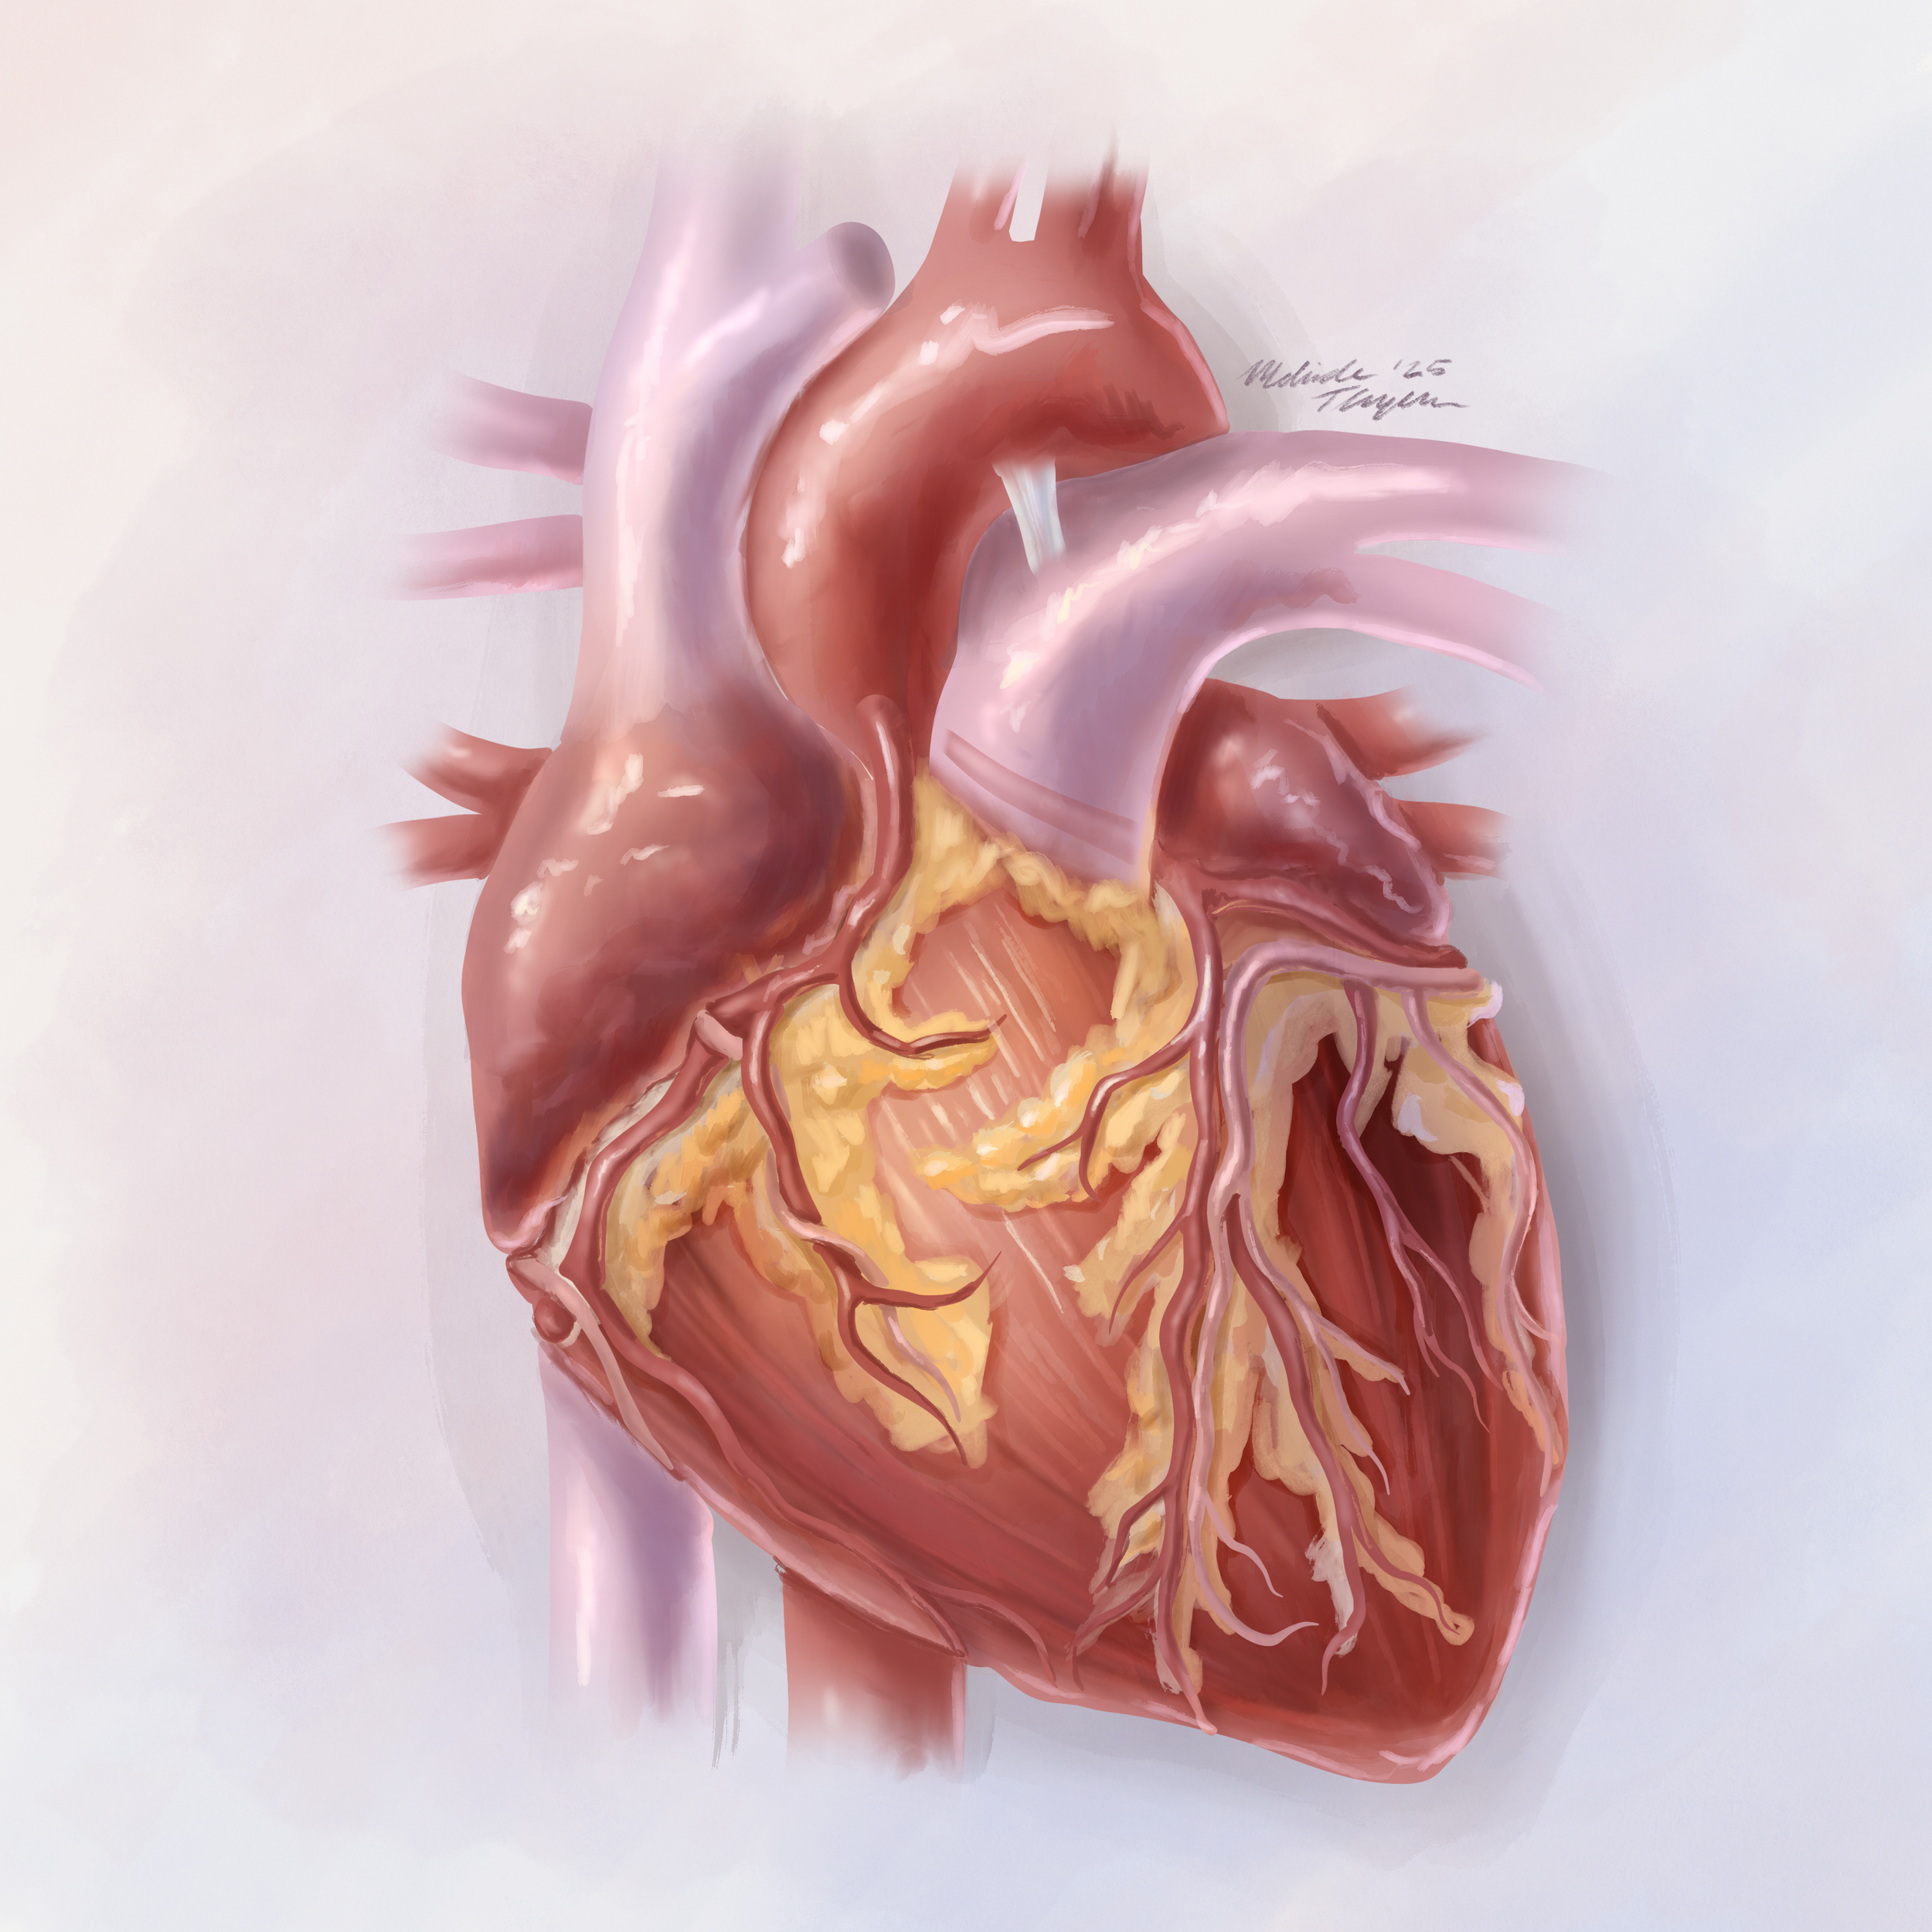

Organ study: The human heart in a painterly style